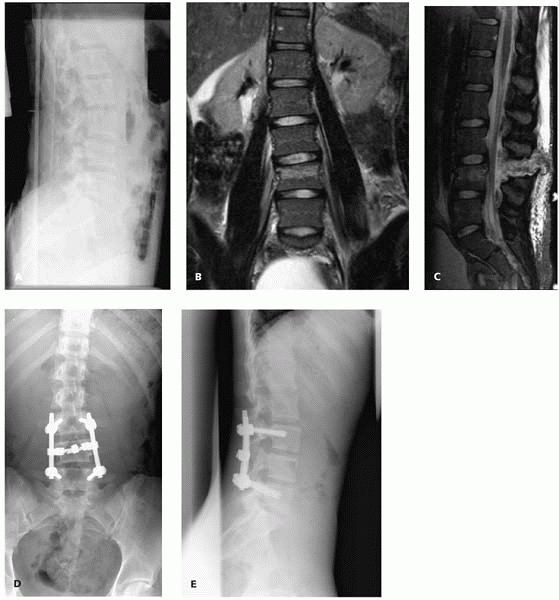

usually compression fractures near the thoracolumbar junction, can be

satisfactorily managed with brace treatment. Injuries with significant

deformity (Fig. 4-18) and/or instability (Fig. 4-19) are usually treated with posterior instrumented spinal fusion.

▪ FIGURE 4-19 L4 chance fracture without neurologic injury (A). The MRI (B, C) shows both a bony component and complete ligamentous disruption, requiring a posterior instrumented spinal fusion (D, E).